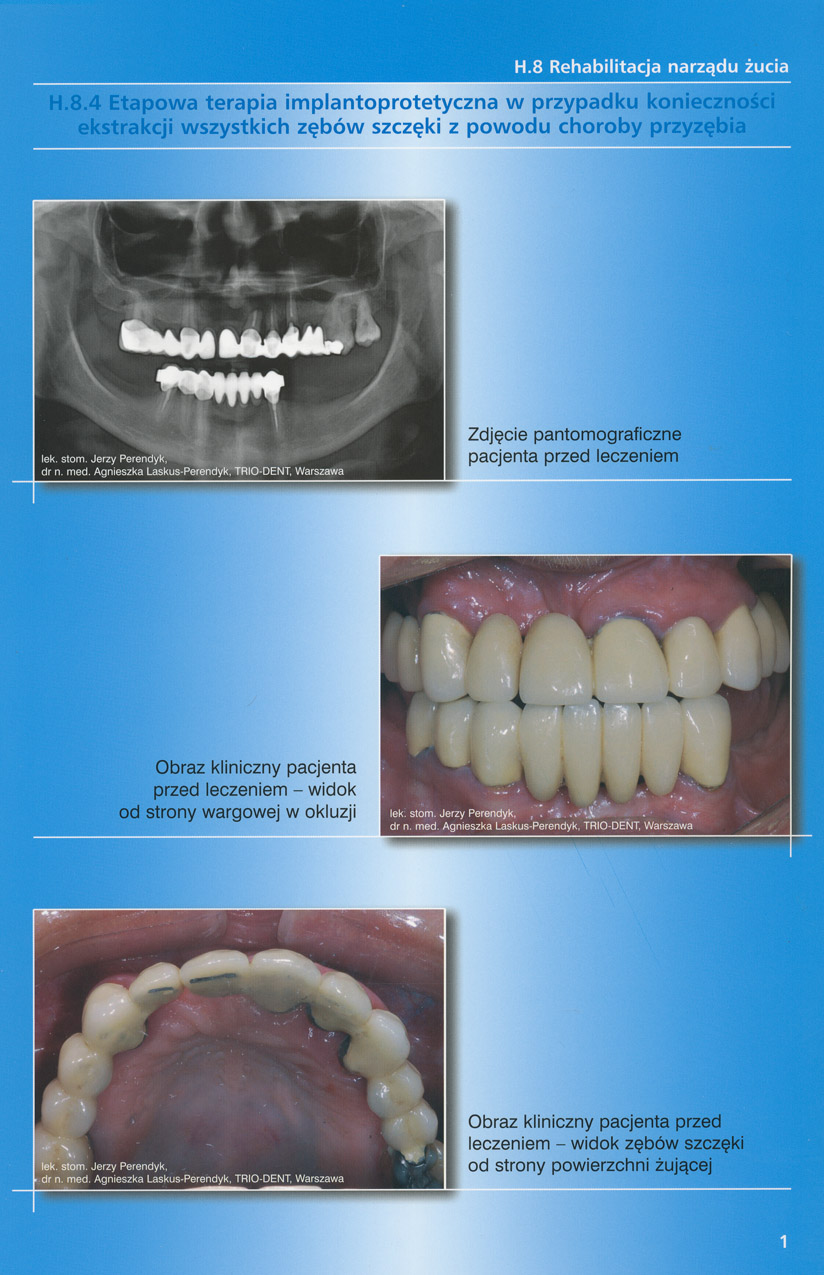

zobacz więcejGaleria przypadków klinicznych, obrazująca proces terapeutyczny od stanu wyjściowego aż do oddania ostatecznej pracy uzupełnienia brakującego uzębienia.